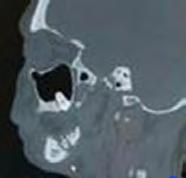

En conjunto con el departamento de odontología y de maxilofacial se solicita tomografía computarizada y gammagrafía con tecnecio 99, donde se confirma el diagnóstico de osteomielitis mandibular con osteonecrosis asociada a bifosfonatos.

Estudios imagenológicos de inicio

En la tomografía computarizada se puede ver una resorción del hueso y una región de secuestro óseo, así como una zona lítica del mismo hueso causada ya sea por una osteonecrosis o por una osteomielitis esto lo encontramos un corte axial a nivel de C2 (Figura 2).

En la gammagrafía se puede observar una zona con una gran cantidad de

células en mandíbula de lado izquierdo (Figura 3).